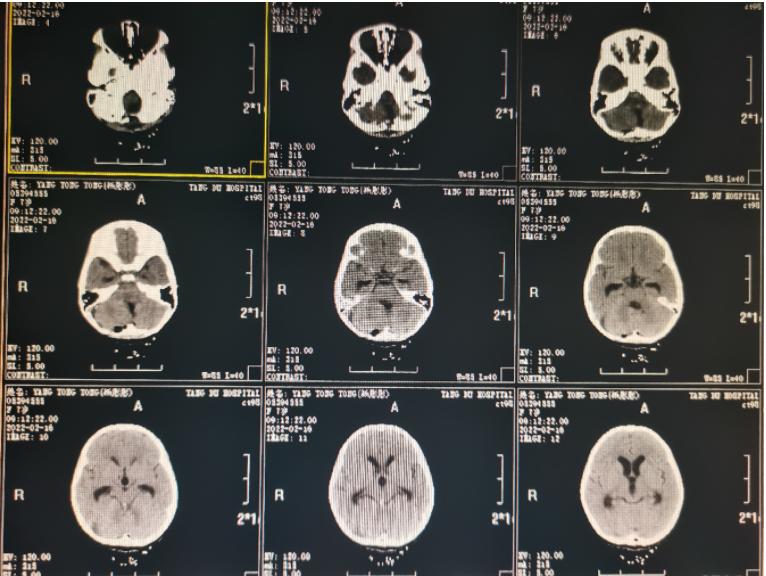

术前影像学资料:

家长在第一时间同意了王超教授的手术方案,本次手术由王超教授亲自主刀,由于室管膜瘤起源于四脑室壁,主要在四脑室内生长,并常常通过正中孔或外侧孔长出四脑室。术中凭借先进的显微镜设备和精湛的手术技巧,完美顺利地完成所有操作,并对切口进行了美容缝合。